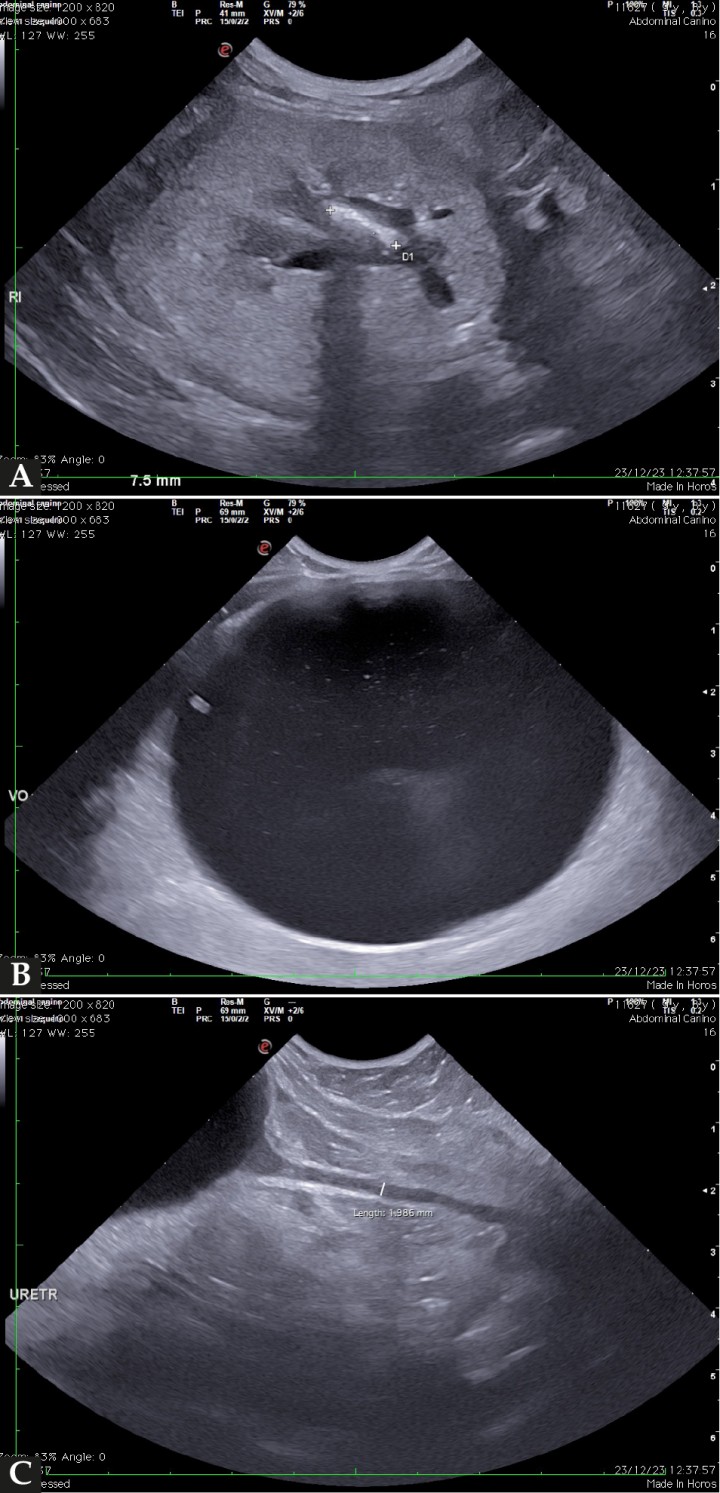

En el caso descrito, se realizó una ecografía abdominal completa utilizando un ecógrafo Esaote MyLabTM X8VET (Esaote S.p.A, Génova) en la que se observó una renomegalia marcada del riñón derecho (6,52 cm) con dilatación de la pelvis renal (3,43 cm), así como destrucción de la morfología renal normal y contenido ecogénico de pequeño tamaño en suspensión (Figs. 3A y 3B).

(A) Imagen ecográfíca del riñón derecho en corte sagital en la que se observa dilatación de la pelvis renal con contenido ecogénico en suspensión y una marcada renomegalia asociada. (B) Imagen ecográfica de un corte transversal del riñón derecho en el que se observa una dilatación severa de la pelvis renal. (C) Imagen ecográfica del uréter derecho dilatado (flecha azul) y tortuoso justo craneal a un ureterolito obstructivo (flecha amarilla).

El uréter proximal derecho se observaba dilatado (3,6 mm) y tortuoso justo craneal a una estructura hiperecoica, amorfa, de bordes mal definidos, de 4,2 x 2,4 mm de tamaño que generaba una fuerte sombra acústica distal (Fig. 3C). Posterior a esta estructura, persistía la distensión ureteral, así como otra estructura de características similares a la descrita previamente. Caudal a este último hallazgo, el uréter se perdía. El retroperitoneo adyacente se observaba engrosado y marcadamente aumentado de ecogenicidad.